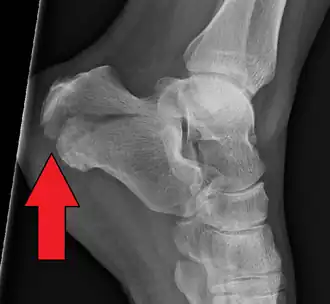

- Fractura de calcáneo.